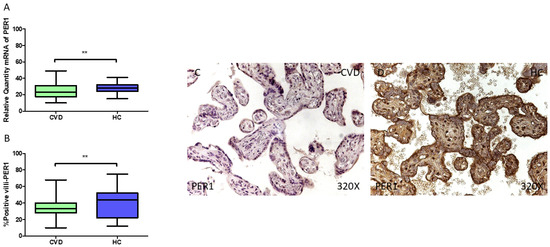

3.1. Placentas of Women Who Undergo Chronic Venous Disease During Pregnancy Display Decreased Expression of Key Circadian Markers